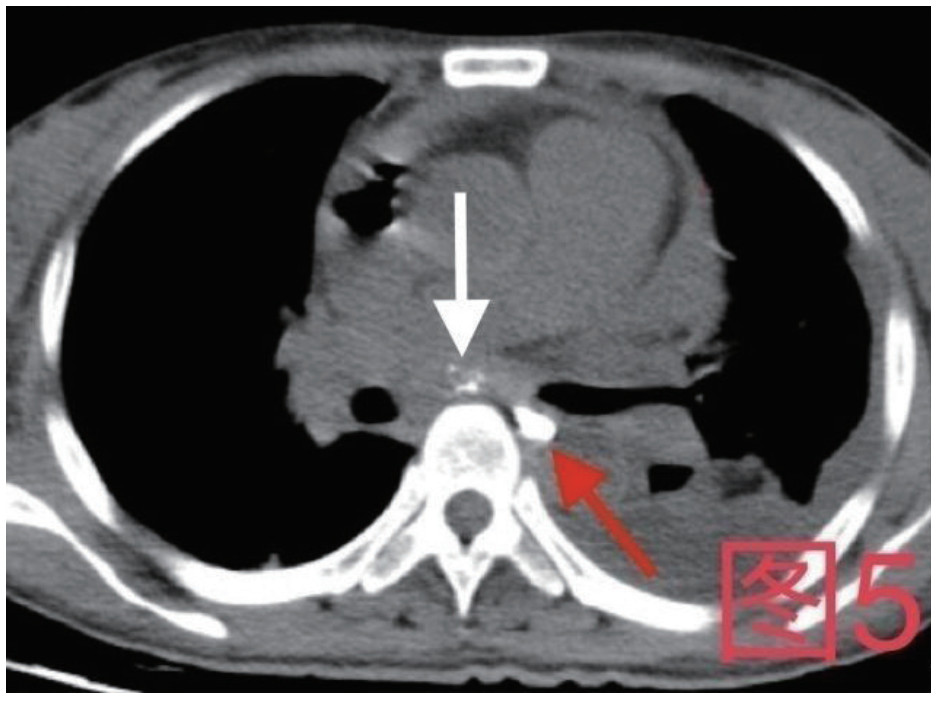

治疗经过:急诊予美罗培南0.5 g,1次/12 h抗感染,补液支持,心包引流等治疗措施,收住感染科后继续抗感染治疗,期间心包积液培养出白假丝酵母菌,加用氟康唑200 mg,1次/d, 口服,心包积液、左侧胸腔积液引流等措施,治疗10 d后复查胸部CT仍有中大量心包积液伴少许积气,纵隔积气;左侧少量胸腔积液,两肺叶间裂少许积液。对照前片(2020.10.26)心包积气及左侧胸前积液有增多,叶间裂积液新发,心包积液略有减少。右肺下叶感染,左肺下叶膨胀不全,较前右肺下叶感染有吸收,左肺下叶膨胀不全新发。考虑不能排除食管纵隔瘘,予口服碘海醇后胸部CT检查(图 3~6):约胸6椎体水平食管纵隔瘘,瘘口为相应水平食管壁右前方可能;胃镜(图 7):食道距门齿25 cm右后壁见一直径约1.0 cm凹陷,内有一小瘘口。胃镜下予钛夹2枚夹闭瘘口(图 8),同时植入空肠营养管。至此患者病情明确诊断食管心包瘘,患者经以上治疗后心包积液、胸腔积液逐渐减少,于11月13日拔除心包及胸腔引流管,因患者签字回当地就诊,予口服莫西沙星、氟康唑带药出院,出院后随访,患者未回当地医院治疗,仅在家中继续空肠营养管饲喂及口服抗菌药物治疗。

图 5 患者卧位第2次口服15 mL碘海醇后,白色箭头所指为纵隔内碘海醇,红色箭头为食管内碘海醇